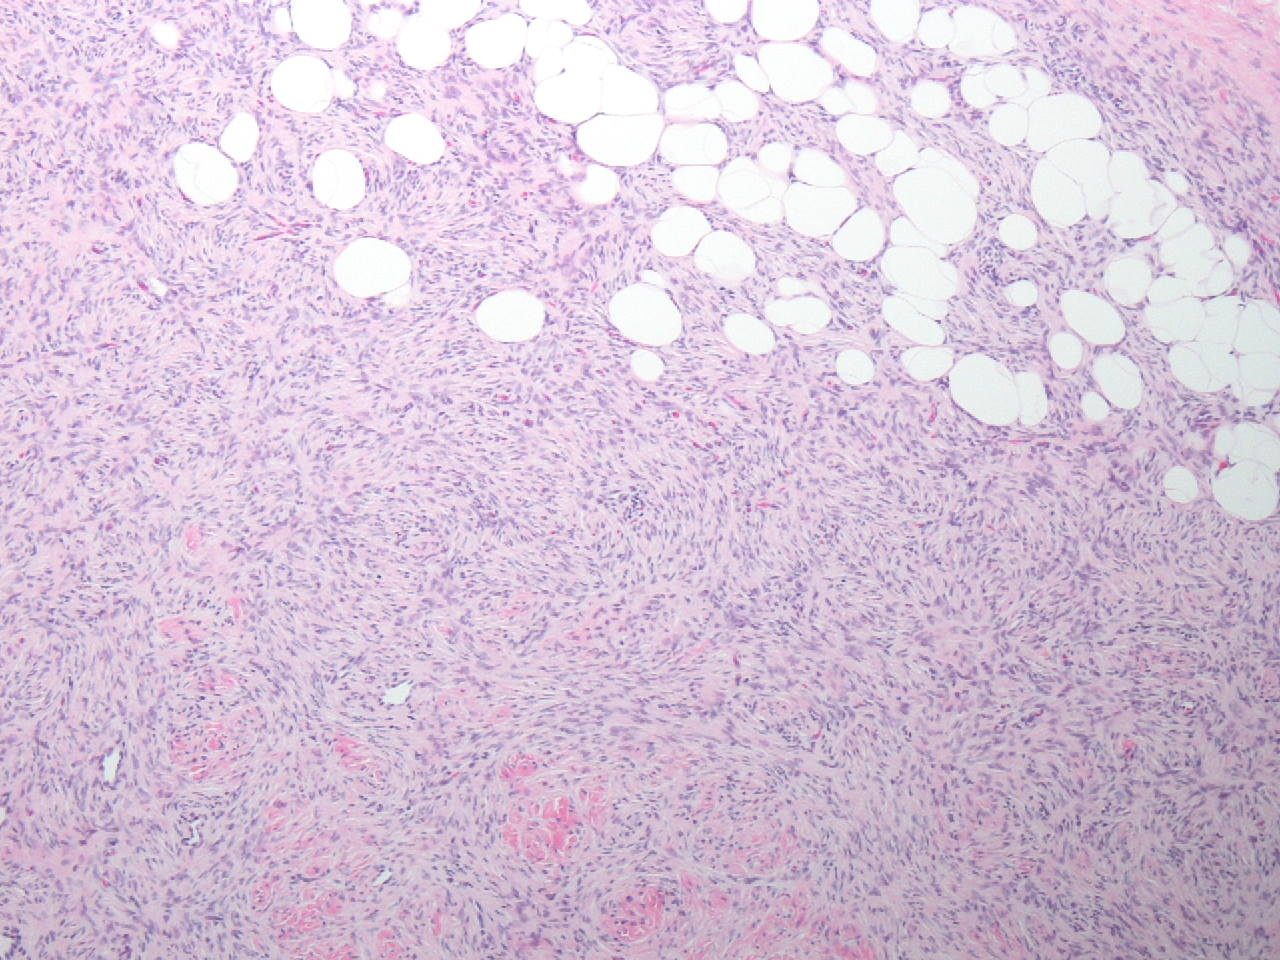

Fig 4Sections show a cutaneous and subcutaneous spindle cell tumor. It is densely cellular and has an obvious storiform pattern. In the deeper aspects of the resection tumor infiltrates between adipocytes creating in some areas a “lace like pattern.” Pigmented cells are present raising the specter of spindle cell melanoma however the tumor is S-100 negative. A smooth muscle actin immunostain is also negative. The positive immunostain is CD34. The pigmented cells are dendritic melanocytes that are hypothesized to colonize the tumor. The vast majority of these tumors contain a Col1A-PDGFR fusion that is the pathogenic driver genomic alteration